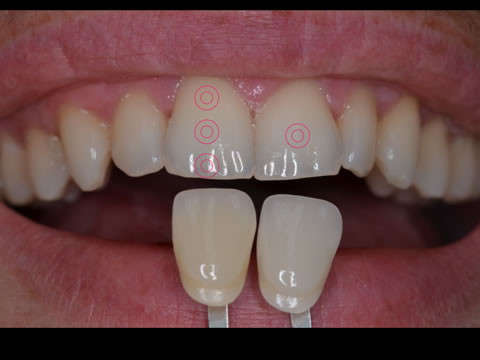

Les recommandations actuelles sont d’utiliser une barrette de référence du teintier au minimum pour donner au prothésiste un élément de comparaison.

A cela peut être ajouté un travail sur la lumière avec les flashs. L’idéal étant de les déporter pour améliorer la perception des états de surface. Un éclairage avec un angle de 45° apporte une lumière douce qui met en valeur les lignes de transition.

Un passage en noir et blanc sera un excellent moyen de contrôler la luminosité.

Il est aussi possible de jouer sur les contrastes pour mettre en avant les zones de translucidité.

Il faudra faire attention au changement de teinte lié à la déshydratation : une dent déshydratée paraîtra plus claire. Il est donc conseillé de prendre la teinte en début de séance et d’attendre la réhydratation de la dent avant de valider le résultat esthétique final.